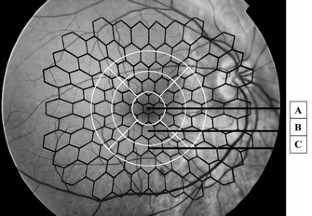

Twenty-six eyes from 18 diabetic patients (13 men), aged 59 years, (range 28–79 years), diabetes duration 15 years, (range 2–27 years), with a macular thickness between 200 and 600 μm were evaluated by mfERG, visual acuity (ETDRS score) and OCT. Mean amplitudes and implicit times of the mfERG responses were analyzed within the four innermost (14 degrees) of the six concentric rings. For comparison with the results from the OCT (diameter of measured area = 6 mm) we analyzed the summed response from the first and second ring (central zone), corresponding to the central area of the OCT. The third(zone 2) and fourth (zone 3)of the four innermost of the six concentric rings measured by the mfERG corresponding to the second and third area of OCT.